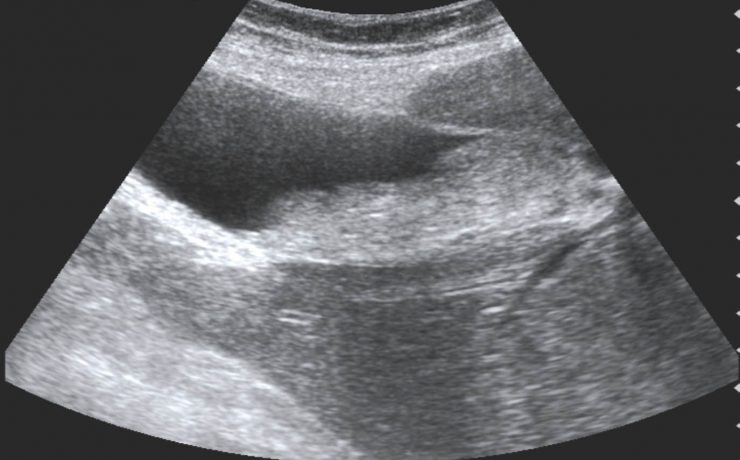

El contenido de este artículo se basa en una mujer de 49 años de edad, con una tumoración abdominal de bordes irregulares de 10×10 cm y que fue sometida a LAPE; Encontrándole dos tumoraciones, una en ovario izquierdo de tipo quístico de 15 cm de diámetro y otra en ovario